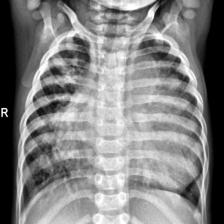

Coronavirus Disease 2019 (COVID-19) demonstrated the need for accurate and fast diagnosis methods for emergent viral diseases. Soon after the emergence of COVID-19, medical practitioners used X-ray and computed tomography (CT) images of patients' lungs to detect COVID-19. Machine learning methods are capable of improving the identification accuracy of COVID-19 in X-ray and CT images, delivering near real-time results, while alleviating the burden on medical practitioners. In this work, we demonstrate the efficacy of a support vector machine (SVM) classifier, trained with a combination of deep convolutional and handcrafted features extracted from X-ray chest scans. We use this combination of features to discriminate between healthy, common pneumonia, and COVID-19 patients. The performance of the combined feature approach is compared with a standard convolutional neural network (CNN) and the SVM trained with handcrafted features. We find that combining the features in our novel framework improves the performance of the classification task compared to the independent application of convolutional and handcrafted features. Specifically, we achieve an accuracy of 0.988 in the classification task with our combined approach compared to 0.963 and 0.983 accuracy for the handcrafted features with SVM and CNN respectively.